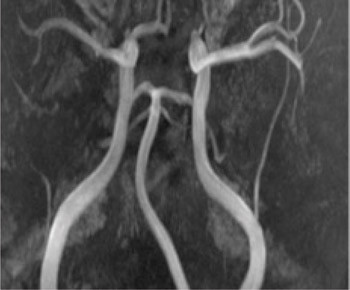

Figure 4

A person in his 20s with known migraine with aura developed infarcts in the right middle cerebral artery and both anterior fields of supply (Figure 1 shows a magnetic tomography diffusion weighted series). Cerebral computed and magnetic tomography with magnetic resonance angiography (MRA) after admission showed normal blood flow and no sign of dissection or vasculitis. Hemicraniectomy became necessary after development of malignant cerebral oedema. MR angiography the first postoperative day showed open arteries (Figure 2 shows an open carotid top (white arrow), normal basilar top (red arrow), and a non-closed circle of Willis, an anatomically normal variant (stars). Testing for illegal drug use, anticardiolipins, anti-nuclear antibodies, neurone antibodies and tumour markers was negative. Transoesophageal echocardiography showed a minimally patent foramen ovale, according to a cardiologic evaluation unlikely to be related to the episode. The patient developed severe brain stem involvement and MR angiography showed narrowing of the posterior branch of the basilar artery (arrows in Figure 3). Arterial vessel spasms were suspected retrospectively. The first suspected vessel spasm, in the right – middle/anterior branch, remained undocumented. The second, in the posterior branch of the basilar artery, was documented postoperatively (arrows in Figure 3). Images of several newly developed infarcts in the posterior circulation are not shown. Three weeks after the hemicraniectomy the angiogram was normalised (Figure 4).